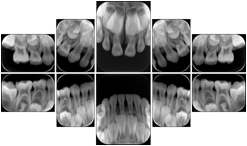

Intra-oral radiography typically involves acquisition of multiple images of various parts of the dentition. Many digital radiographic systems offer customized templates that are used for displaying the images in a study on the screen. These templates may also be referred to as mounts or view sets. The Structured Display Object represents a standard method of encoding and exchanging the layout and intended display of Structured Displays. A structured display object created in this manner could be stored with a study and exchanged with images to allow for complete reproduction of the original exam.

1. A patient visits a General Dentist where a Full Mouth Series Exam with 18 images is acquired. The dentist observes severe bone loss and refers the patient to a Periodontist. The 18 images from the Full Mouth Series along with a Structured Display are copied to a DICOM Interchange CD and sent with the patient to see the specialist. The Periodontist uses the CD to open the exam in his Dental Radiographic Software and consults via phone with the General Dentist. Both are able to observe the same exam showing the images on each user's display using the exact same layout.

Intra-oral Full Mouth Series Structured Display

Figure OO-1. Intra-oral Full Mouth Series Structured Display